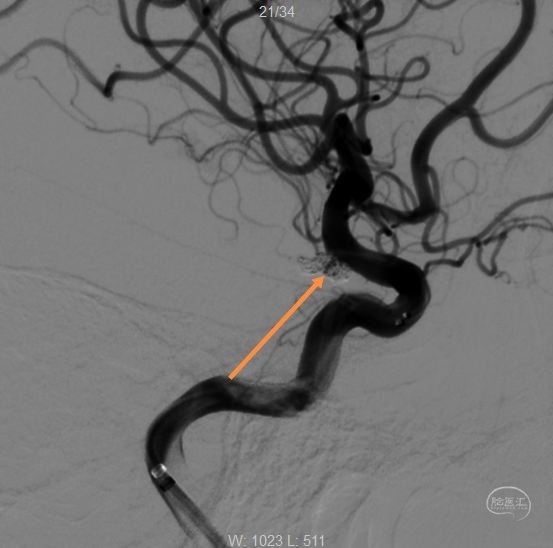

术后工作位造影

换角度观察,栓塞满意。

正位